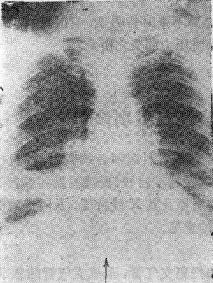

2.支气管腔外压性梗阻 如淋巴结肿大、血管环压等图115-1右下肺不张

图115-1 右下肺不张